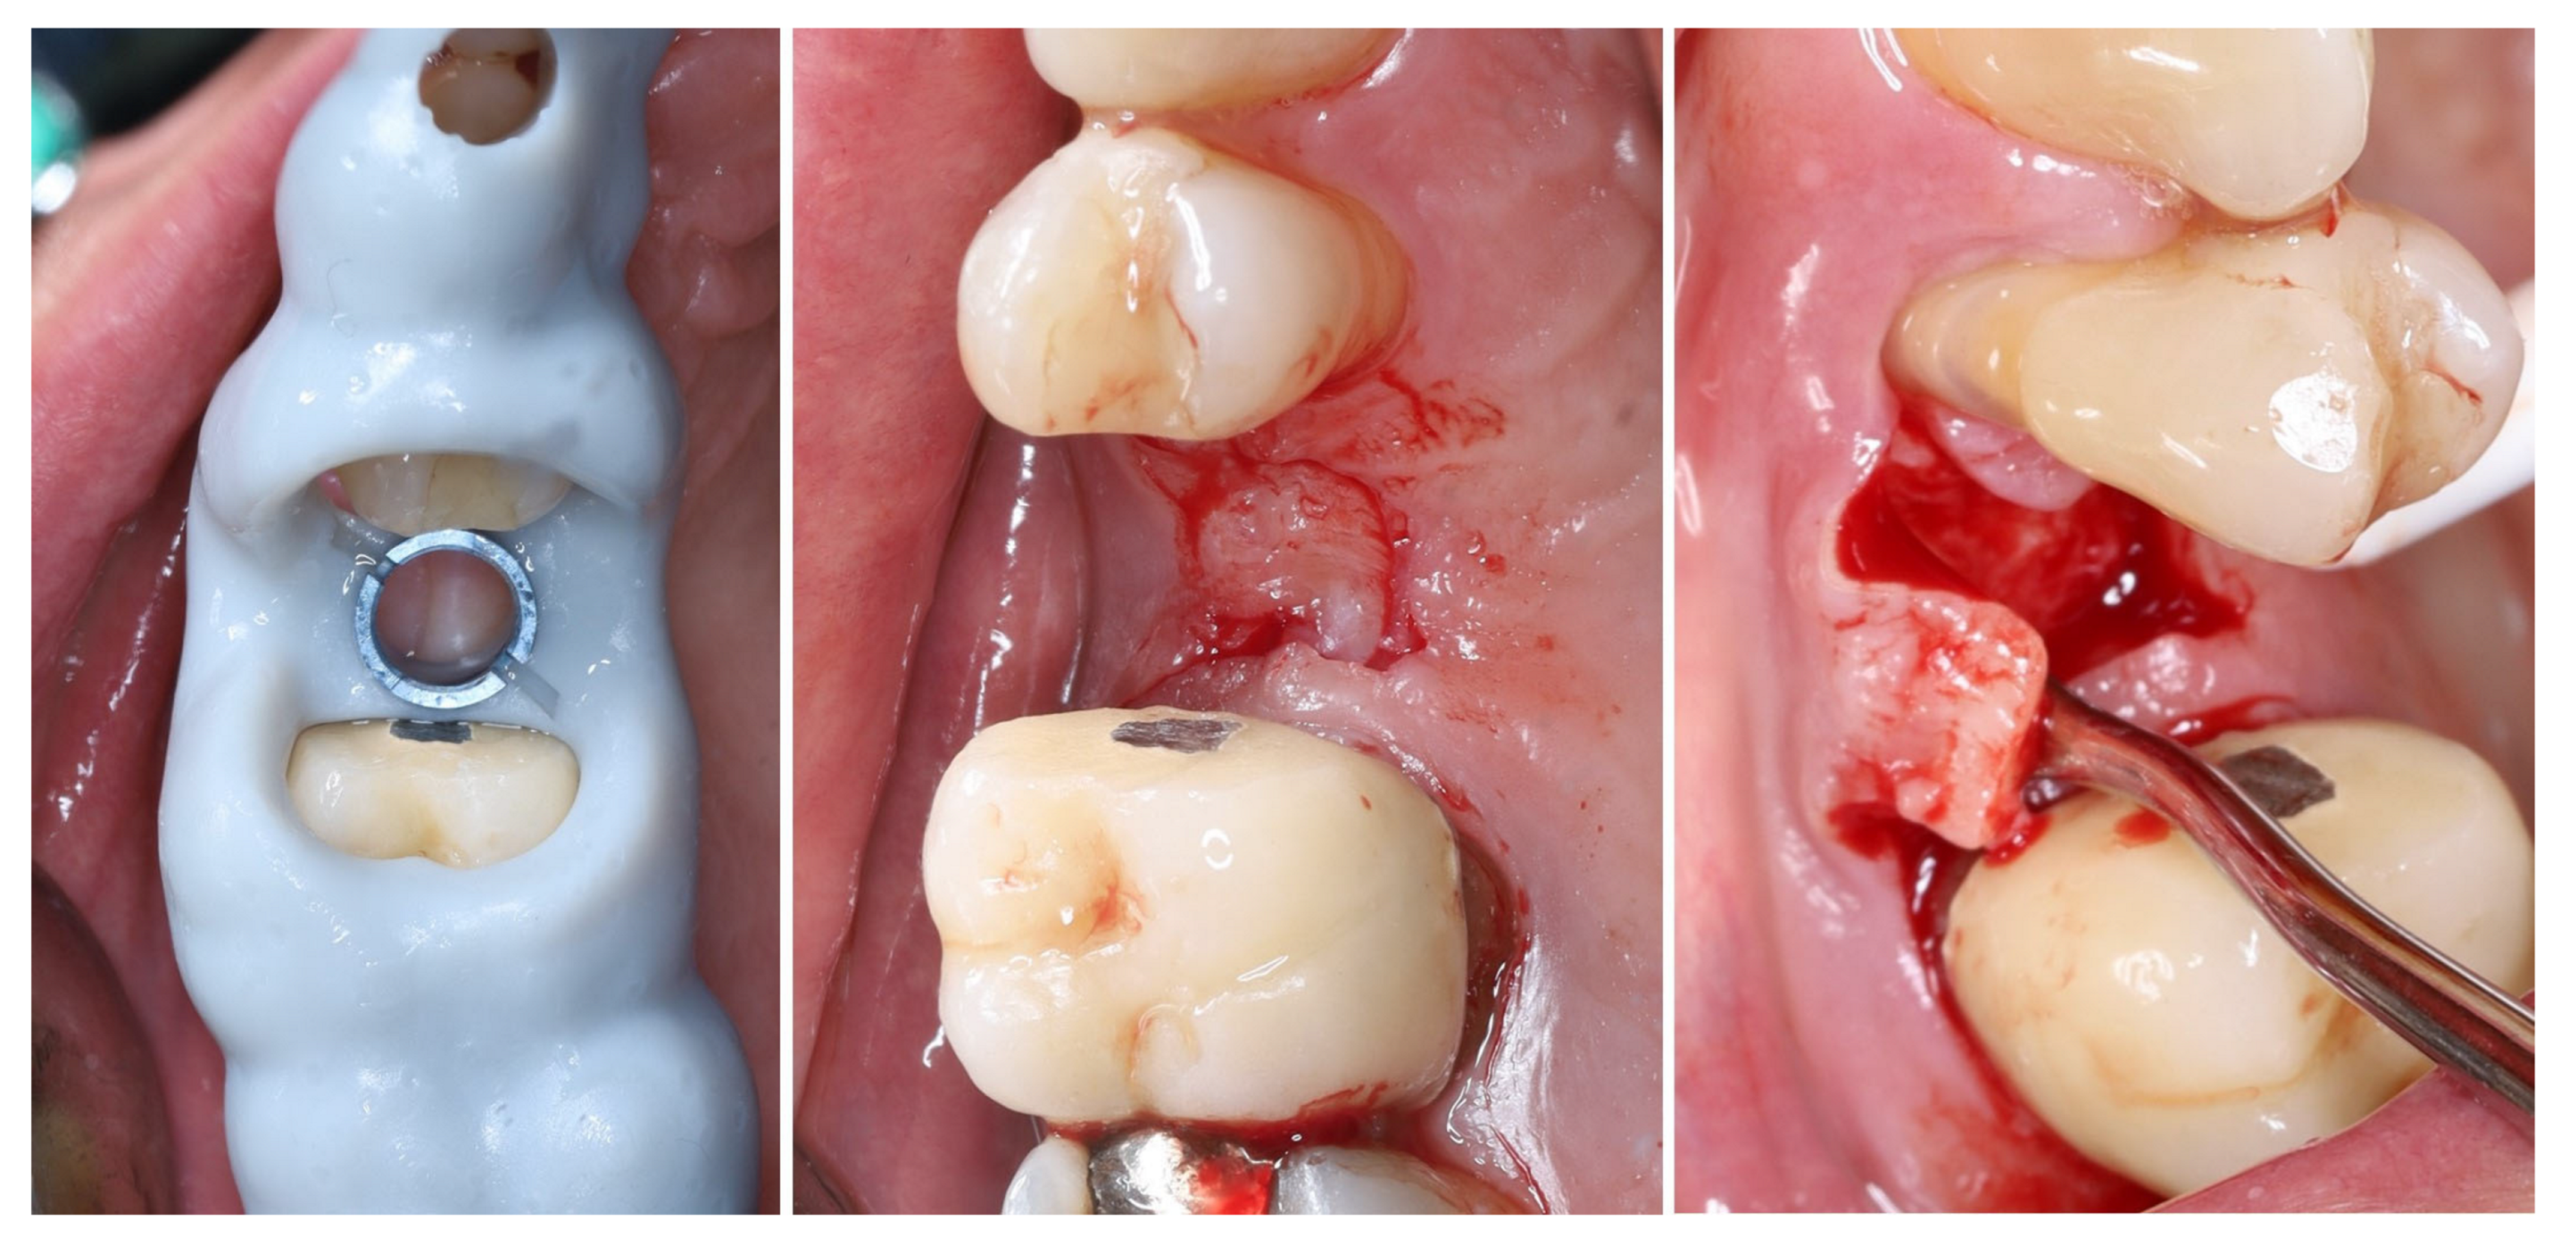

2. Materials and Methods—Clinical Case